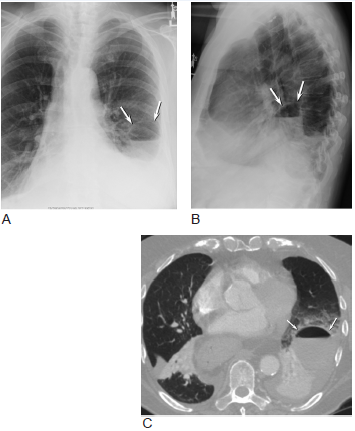

4,绿脓假单胞菌 胸片可见典型的支气管肺炎,包括节段性,多灶性,斑片状

(b,c)48岁男性肺炎伴气管支气管巨大症患者横断面ct(b)和冠状ct(c)

有些病例具有支气管肺炎,即小叶性肺炎的特点.

病例 :支气管肺炎.

支气管肺炎ct图片

支气管肺炎CT